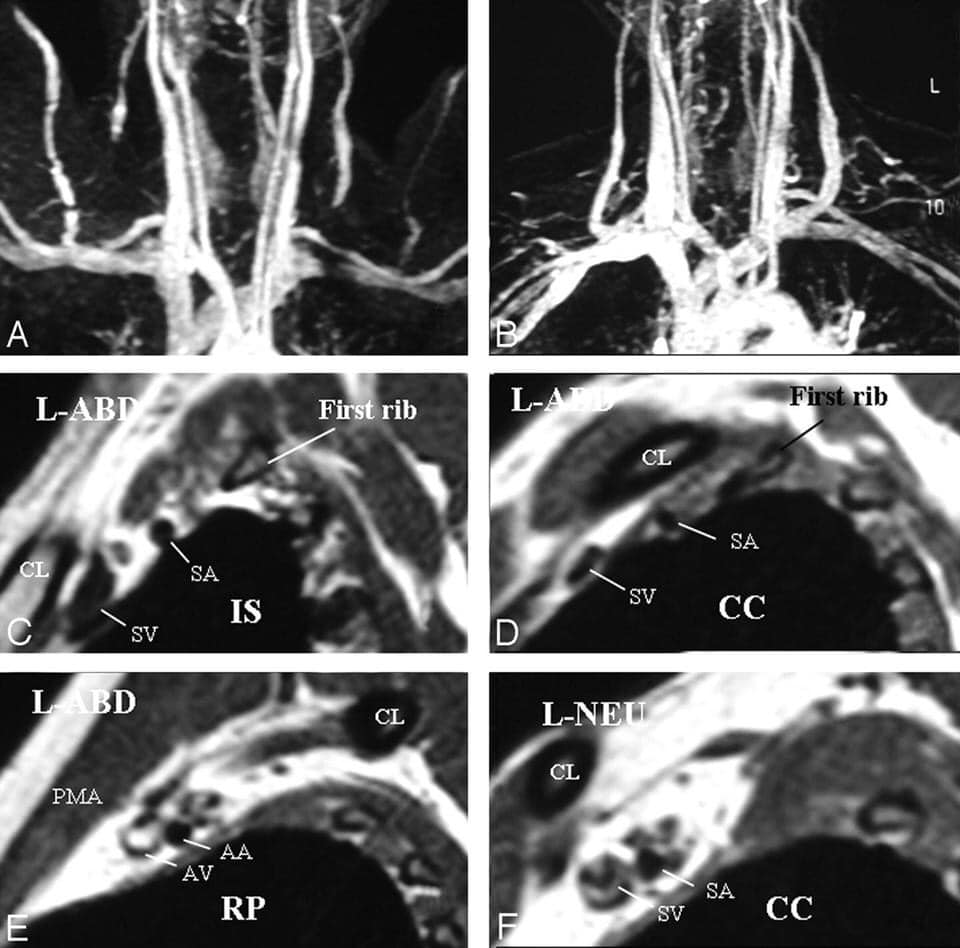

*Chụp cộng hưởng từ (MRI): Những hình ảnh này có thể giúp xác định vị trí và nguyên nhân gây ra ép các dây thần kinh của đám rối thần kinh cánh tay hoặc động mạch dưới đòn. Những hình ảnh quét cũng có thể tiết lộ bất kỳ dị tật bẩm sinh – chẳng hạn như một dải sợi kết nối xương sống của bạn với xương sườn hoặc xương sườn phụ có thể là nguyên nhân gây ra các triệu chứng.